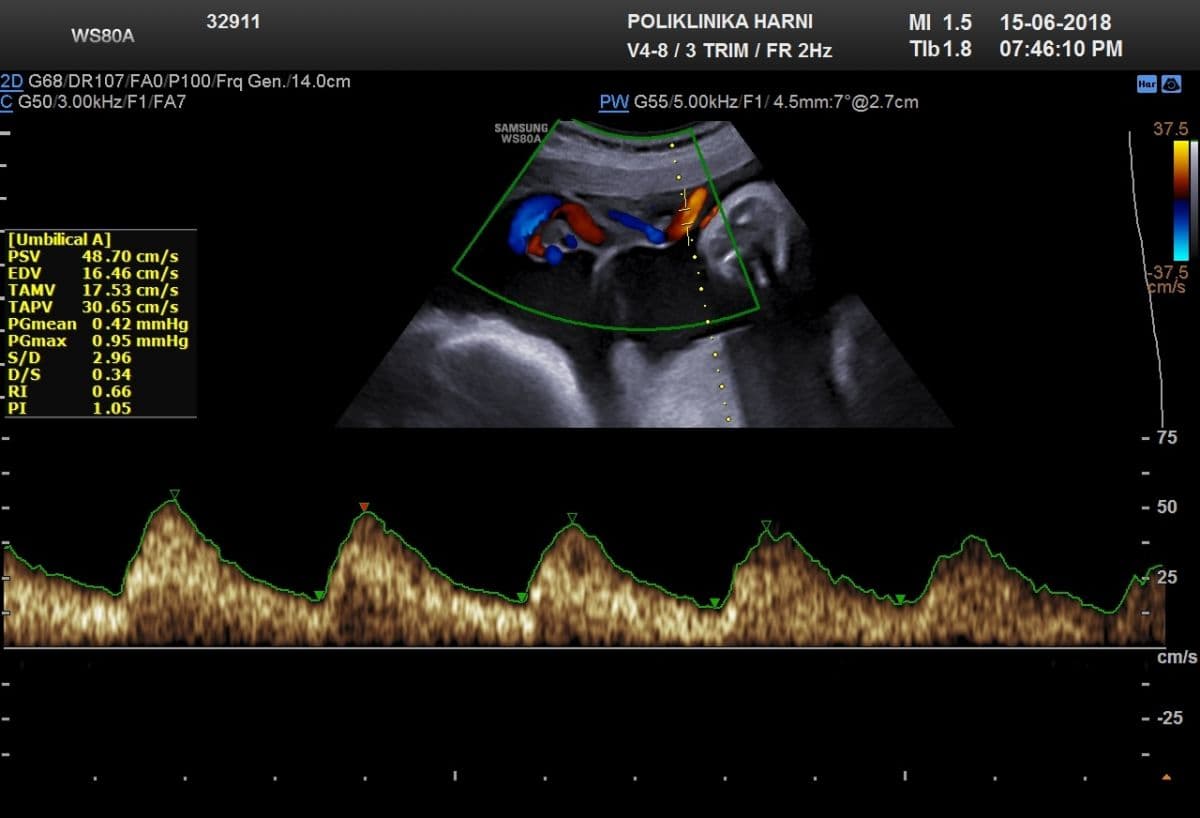

Kolor Dopler feto-maternalnih krvnih žila

Neki znanstvenici preporučuju rutinski pregled obojenim Dopplerom između 30. - 34. tjedna trudnoće kod svih trudnica. Zbog specifičnosti u razvitku feto-maternalnih krvnih žila obojeni Doppler se preporučuje načiniti tek nakon 20. tjedna trudnoće. Izuzetak je jedino sumnja na anomalije fetalnog srca ili krvnih žila. Mjerenje indeksa protoka kroz fetalne krvne žile i pupčanu arteriju može pretkazati fetalnu patnju i do mjesec dana ranije, uslijed nepravilnost razvoja i/ili funkcije fetoplacentarne jedinice.

Ranije je opisano da se tehnika obojenog Doplera primjenjuje i ranije, u okviru otkrivanja odsutnosti ili reverznog protoka krvi kroz duktus venozus ili na srčanoj valvuli između desne pretklijetke i klijetke / trikuspidalna regurgitacija. U 70-90% fetusa s kromosomskim abnormalnostima se pri ovom pregledu između 11.-14. tjedna trudnoće u tim krvnim žilama nalazi inverzan protok, pa je mjerenje protoka kroz duktus venozus tehnikom obojenog Doplera sastavni dio svakog ozbiljenijeg traganja za ultrazvučnim biljezima kromosomopatija.